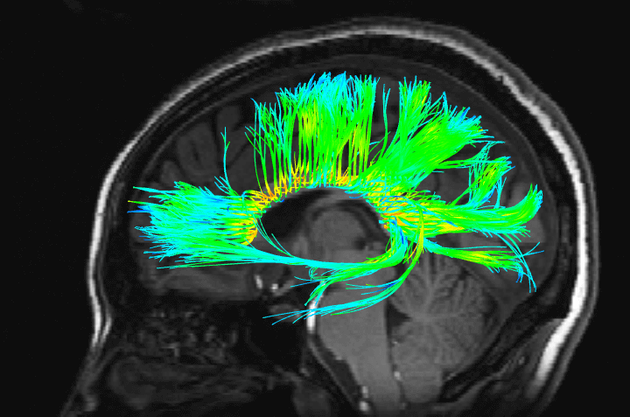

为什么大脑的神经元网络感觉像是一种体验?

大脑的功能性核磁共振(fMRI)扫描图像

理解意识可能是我们这个时代最大的科学挑战。生理的东西(如电脉冲)将如何解释心理的东西(如梦或自我感觉)?为什么大脑中的神经元网络给人以一种体验的感觉,而电脑或者人群的社交网络却没有这种感觉?